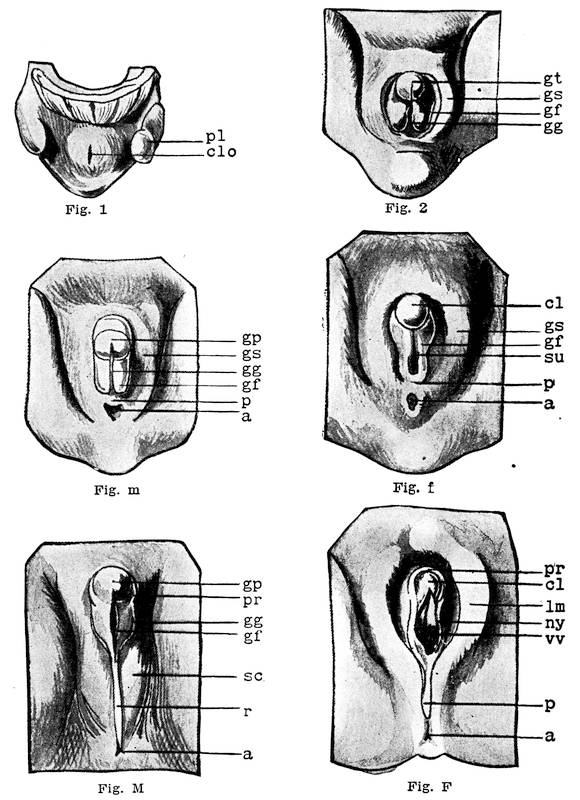

Wolffian body, cloaca, ducts of Muller, ureter, kidney, genital ridge, sex-gland, allantois, bladder, urachus, sinus urogenitalis, urethra, perineum, anal membrane, male internal sex-organs, female internal sex-organs, genital swelling, genital tubercle, groove, male external genitals, female external genitals.

D. The External Genitals

At the time when the urethra, the sexual ducts and the intestine still open into the sac-like tube, the so-called cloaca, there is distinguishable on the exterior surface of the body, corresponding to the position of the cloaca, a certain depression called the cloacal depression. When the intestine is separated from the cloaca by the septum, the later perineum, the exterior cloacal depression is cut into two, the anal and the urogenital depressions. Between the urogenital depression, later called the genital groove, exteriorly and the urogenital sinus interiorly, there is only a dividing membrane, the urogenital membrane which later on breaks through and transforms the entire sinus into a shallow depression, termed the vestibule.

Before the urogenital sinus has opened to the exterior the

mesenchym surrounding the urogenital depression exteriorly

begins to thicken and produces an encircling elevation, the genital

swelling. On the ventral side within this swelling appears

a projection, the genital tubercle, which is thus surrounded by

the genital swelling. The tubercle soon increases in size, so that

the urogenital depression, now called the genital groove, becomes

partly situated at its under aspect (Cut 5, Fig. 2). The lips of27

28

this genital groove thicken and form the two genital folds. All

these four organs are common in both sexes and represent the

asexual or bisexual state of the external genital organs.

F. The Female External Genitals

In the female the vestibule, or the shallow depression which was formed through the breaking through of the urogenital membrane, remains open throughout life, and is termed the vestibule of the vulva. From the sides of the lower part of the sinus a pair of evaginations are formed and give rise to the Bartholinian glands. The vestibule being in fact the open sinus urogenitalis, the urethra and the vagina naturally have their orifices in the same.

The genital tubercle ceases to grow in the female and becomes the clitoris. The genital folds or the lips of the vestibule become prolonged and form the labia minora or the nymphae. The genital swelling increases in size through adipose and fibrous tissue. The part situated on the ventral side of the clitoris becomes the mons veneris, while the lateral parts are converted into the labia majora of the vulva.